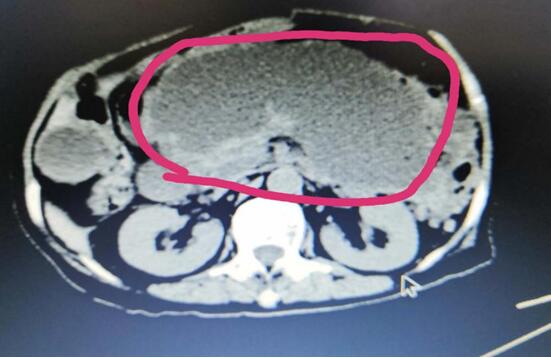

患者A,女,72歲,1年前因急性出血壞死性胰腺炎,曾行腹腔鏡下壞死胰腺組織清創(chuàng)+外引流術(shù),術(shù)后出現(xiàn)急性胰腺假性囊腫,囊腫越來越增大,以至于病人不能做下蹲和彎腰動作,給生活造成極大不便。本次患者因急性腹痛入院,入院診斷為:胰腺巨大假性囊腫并發(fā)出血,重癥胰腺炎清創(chuàng)術(shù)后。

(術(shù)前腹部CT顯示胰腺巨大假性囊腫)